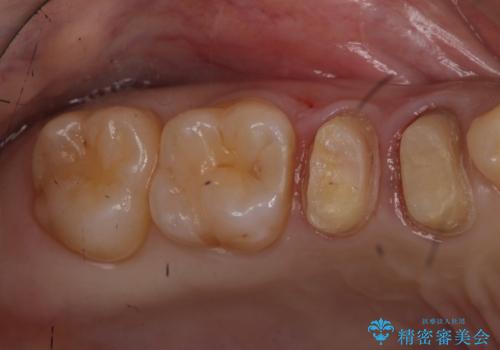

ラバーダム治療ではなかったとのことで、唾液の侵入を防ぐ、当院でのラバーダム治療のメリットを説明しました。

前回の治療がうまくいかなかった原因として、根の中がまだ汚い状態で、根の先だけを切ってもうまくいかない可能性があったことを説明し、根管治療をやり直すことになりました。

必ずしも根管治療がうまく行くかわからないため、抜歯してインプラント(またはブリッジ)にする選択肢もありましたが、なるべく抜歯を避けたいとのことで、根管治療を選択されました。

なお、根管充填にはMTAを使用しました。